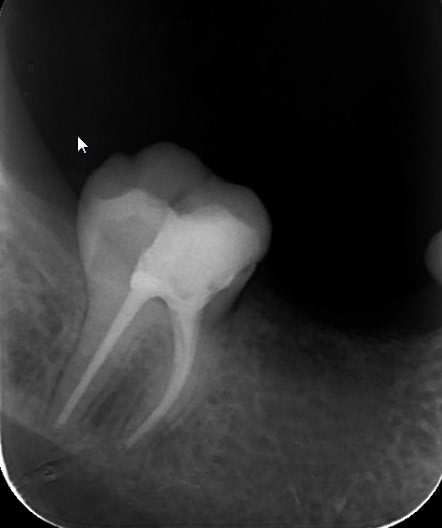

Bon j'ai repris une radio de la 47,une fois le bridge posé, pour contrôler l'adaptation et en même temps vérifier que je ne suis pas à 2 mm du dôme apicale radiologique.

D'après la mesure effectuée sur le logiciel cliniview, je suis à seulement à 0.6 mm de l'apex radiologique.